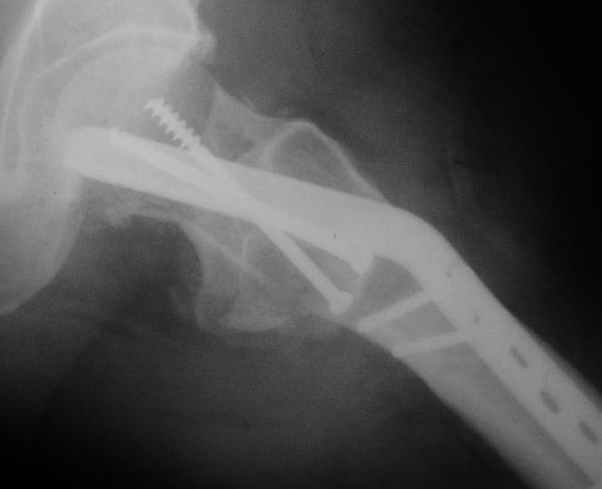

Мужчину 56 лет оперировали у нас в августе 2003 г. - вальгизируюшая остеотомия из-за позднего (через 2 мес. после травмы) поступления с переломом шейки бедра (картинки 1,2). Курильщик, соматической патологии не было. Сейчас поступил с жалобами на проблемы в области тазобедренного сустава, на снимках 3,4 видно вырезывание клинка.Чтоб можно посоветовать в этой ситуации? Заранее спасибо.

A male 56 years old was operated in Aug 2003 - valgus osteotomy performed because of delayed admission with neck fracture (2 months) images 1,2. Smoker, no other major medical problem. Now he re-admitted with the images 3,4.What would you do in the situation?THX in advance.

The osteotomy seems to be showing bony union. (New bone at the medial aspect). There is a big step in the union. The distal fragment is way out laterally.There is overiding of the neck over the head. The screws are out superiorly and the blade also coming out. There is no union of the neck fracture. The head does not seem to be normal- distorted in shape and probably starting of AVN too.